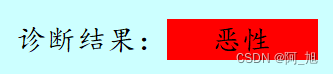

诊断结果区域:分别用'绿色'、‘黄色’、‘红色’背景代表‘正常’、‘良性’、‘恶性’这3种类别的检测结果。

显示效果如下: